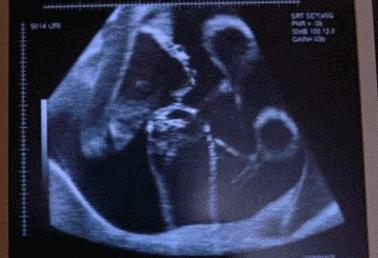

整个孕期,小凤没有任何不适和异常症状,所以她几乎没有上医院进行产检,唯一做的一次B超,是在宝宝28周的时候,显示宝宝脐带绕颈,其余一切正常。此后,大意的小凤便一直在家待产,直到39周被医生诊断为“胎死宫内”。

孕7~8周时,超声波检测可见到子宫内胚芽有轻微波纹状运动。